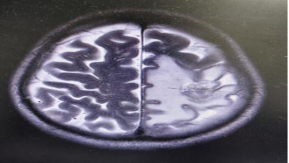

患者于2025年4月22日開(kāi)始行顱腦再程放療,分別于2025年4月27日及5月19日給予貝伐珠單抗300mg抗血管生成治療。期間輔以甘露醇、地塞米松脫水降顱壓等對(duì)癥支持治療。整個(gè)治療過(guò)程順利,患者未發(fā)生癥狀性放射性腦壞死、頭痛、惡心嘔吐等嚴(yán)重不良反應(yīng)。放療結(jié)束后復(fù)查顱腦MR可見(jiàn)腫瘤大小1.7x1.7cm,水腫帶明顯減輕(圖2),療效評(píng)價(jià)PR,右下肢肌力較前明顯恢復(fù)。

2.顱腦MR可見(jiàn)轉(zhuǎn)移瘤及水腫帶明顯減小